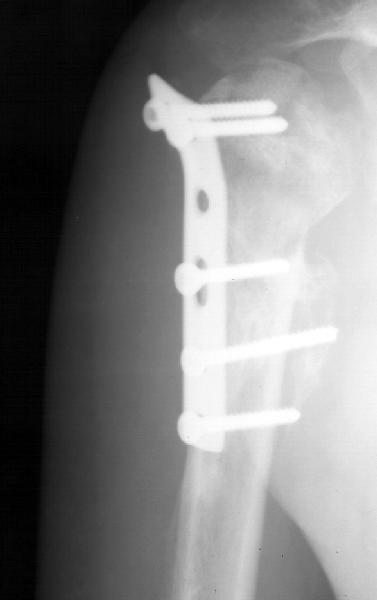

Мужчина 25 лет 16 августа 2002 г. в автоаварии получил перелом шейки плеча (снимок 1); 5 сентября в городской больнице выполнен остеосинтез пластинкой (снимок 2).К настоящему времени попал к нам на разработку ввиду выраженной контрактуры плечевого сустава. В течение последнего месяца беспокоят умеренные боли в области плечевого сустава, усиливающиеся при разработке, еще и торчит край пластинки. Нынешняя рентгенологическаякартина на снимках 3 и 4. Головка плеча уменьшается, сращение сомнительное.Кроме удаления пластинки, что еще на сегодня целесообразно сделать?Заранее спасибо.

The current xrays indicate failure of the implant with losening. I would make sure there was no evidence of infection ( exam,ESR,CRP etc.) . I would agree with implant removal . I think this would be a suitable case for a circular ring fixator and compression, either a standard IIizarov or Taylor Spatial frame would be appropriate. I note from your previous cases that you have a high level of experience with this method.